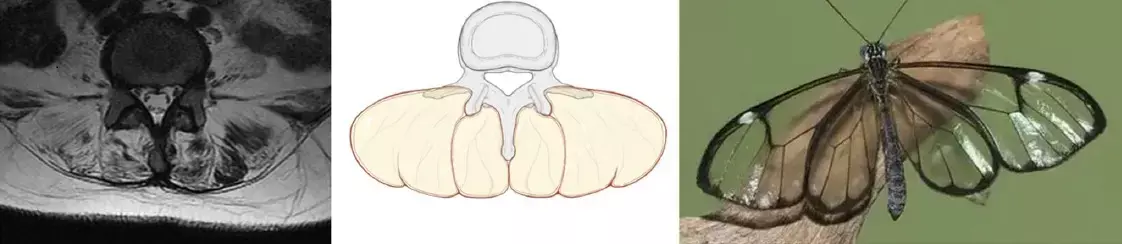

Muscle atrophy and fat infiltration result in extensive fat deposits in the posterior paraspinal muscles, which, when viewed on T2 axial MRI along with the vertebral body and spinous processes, produces a distinctive imaging appearance similar to that of a glassy-winged butterfly (Greta oto), which can be referred to as the “Greta oto” sign.

There were three females and one male, aged from 38 to 55 years. MRI examinations showed significant atrophy and fat infiltration of the bilateral erector spinae muscles, as well as varying degrees of atrophy observed in the multifidus muscles. The fatty degeneration in the erector spinae and multifidus muscles, together with the vertebral bodies and spinous processes, produced a distinctive imaging manifestation resembling a “Greta oto” sign on axial T2-weighted MRI scans in all patients. Ultimately, all four patients were referred to the neurology department, where the diagnosis of myopathy was confirmed by muscle biopsy (one myopathy with early-onset Paget disease and frontotemporal dementia type 1 (IBMPFD), one HMGCR antibody-positive myopathy, one myotonic dystrophy and one limb-girdle muscular dystrophy.